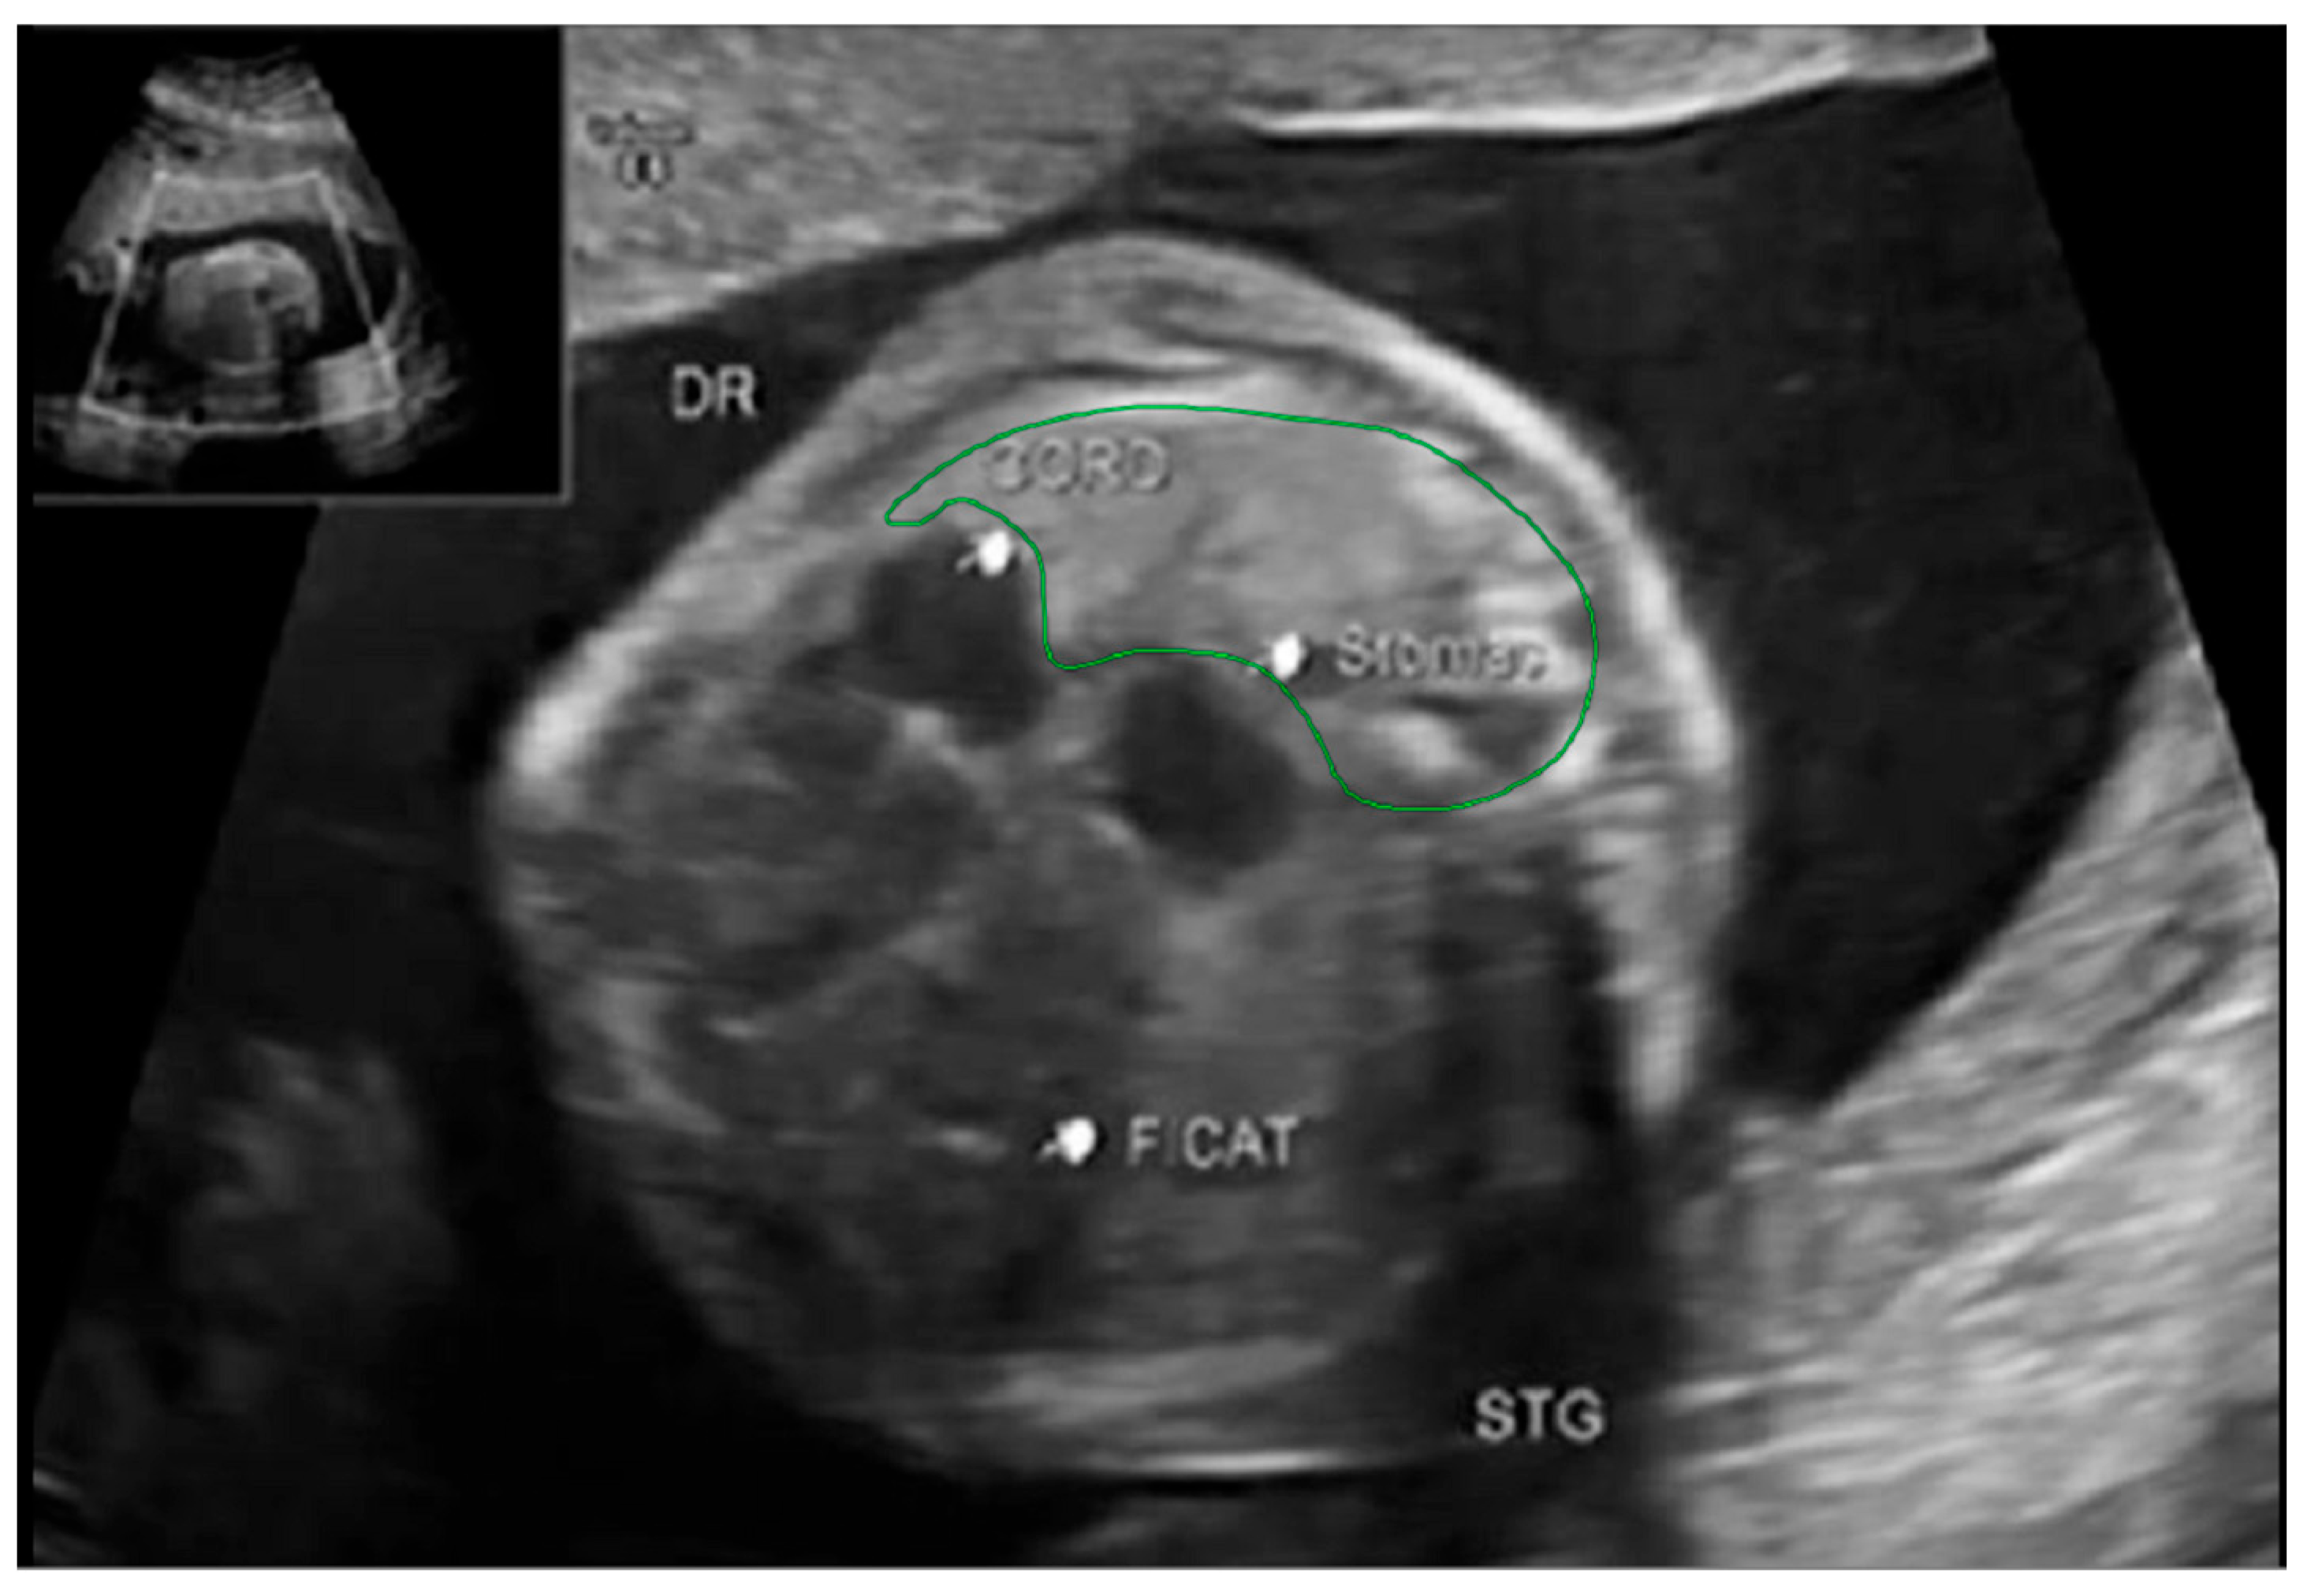

The thoracic area, however, was measured on the interior margin of the ribs, the spinous processes, and the vertebral body. Figure 7 and Figure 8.

Figure 8. Ultrasound axial four-chamber image of the fetus showing how to measure the thoracic area, using the RadiAnt DICOM Viewer program, version number 2022.1.1. The green line represents the thoracic area.